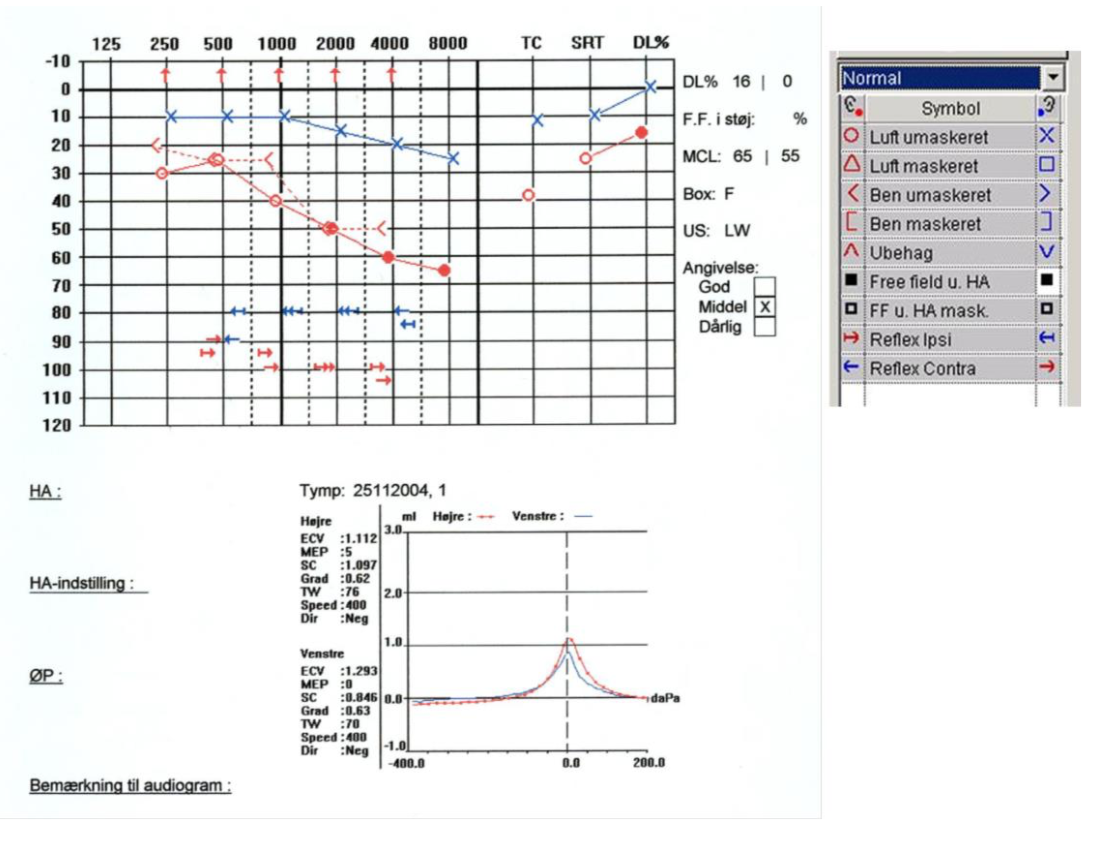

En 55-årig mand søger egen læge, fordi han har fået tiltagende problemer med at høre på venstre øre igennem 2 måneder. Han klager desuden over tinnitus på

øret. Han får lavet nedenstående audiogram ved en øre-næse-hals læge (rød = højre og blå = venstre øre).Venstre trommehinde er intakt, men virker retraheret.Hvilken diagnose giver audiogrammet og tympanogrammet i kombination med anamnesen mistanke om?

a. Mb. Ménière

b. Støjbetinget høretab

c. Presbyacusis

d. Vestibularis-schwanom

e. Sekretorisk otitis media

*e. Sekretorisk otitis media

K11 E17

Hvad vurderer du ud fra ovenstående?

a. Den venstresidige refleks kan ikke fremkaldes

b. Den højresidige refleks kan ikke fremkaldes

c. Der er overvejende konduktivt høretab på højre øre

d. Skelnetabet er størst på venstre øre

e. Hørenedsættelsen er cochleær på højre øre

*e. Hørenedsættelsen er cochleær på højre øre